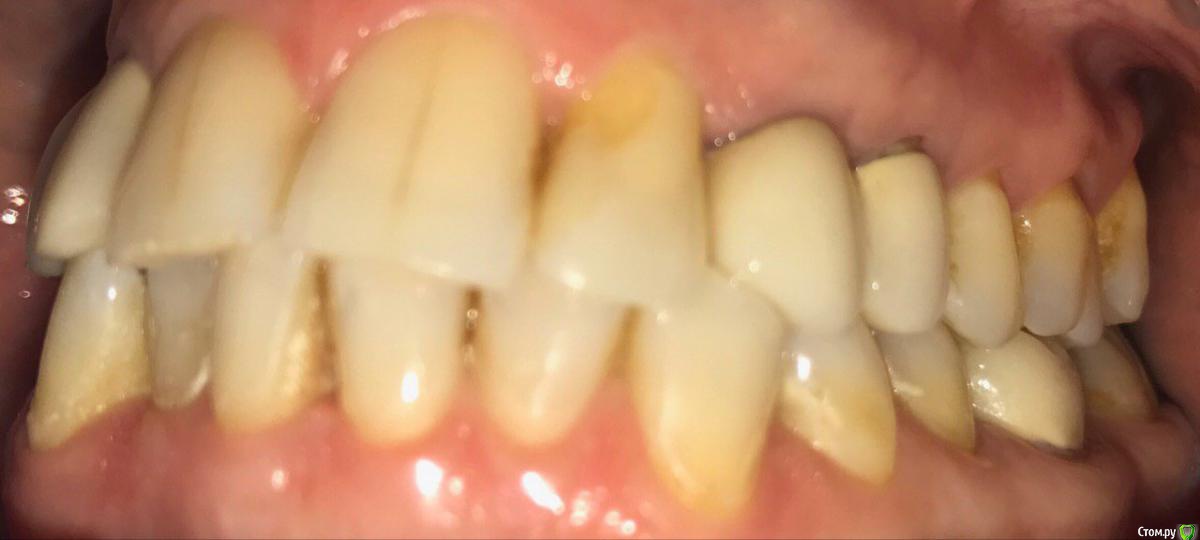

ksenistom Опубликовано 13 декабря, 2016 Поделиться Опубликовано 13 декабря, 2016 Пациентка И.,55 лет,хочет голливуд на обеих челюстях,в виде циркониевых коронок,справа сверху снят мостовидный протез,где установлены 2импл. неделю назад и удалён ретинированный клык в обл 13зуба(фото панорамы нет),поэтому эту сторону пока не трогаем,в области 46 планируется имплантация, 36зуб-вкладка+коронка,в области скученных нижних зубов сделан воксап.Вопрос в том,с чего начать?! Ссылка на комментарий

ksenistom Опубликовано 13 декабря, 2016 Автор Поделиться Опубликовано 13 декабря, 2016 План есть,я хочу начать слевой стороны,обточить верх и низ,навстречу друг другу,потом фронт и в последнюю очередь правую сторону,все под временные,оттиски,примерка каркасов,готовой работы и фиксация.От ортодонта отказалась из-за длительного лечения Ссылка на комментарий